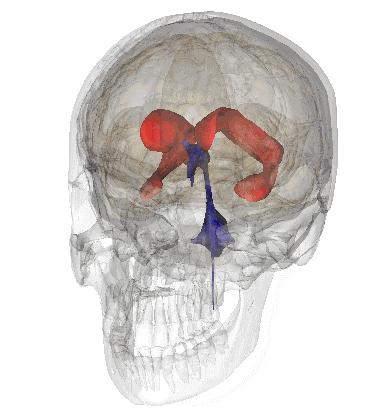

脑室系统

2

大脑供血动脉3D扫描CT成像